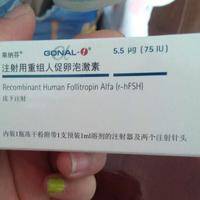

问题描述:我在制定好试管治疗方案后,医生就说要在月经开始的时候再做促排治疗。今天开始打促排针了,我看给我打的是果纳芬。因为后面还要打很多针,所以护士叮嘱说打肚脐周围就可以。但我忘记问打左边还是又变了,所以想问问打哪边的促排效果更好?最佳回答:果纳芬打在肚子左边还是右边的促排效果都差不多。果纳芬通常是通过皮下注射的方式给药。考虑到方便的情况下,一般会建议在肚子上面打,具体选择左边还是右边其实并没有多...